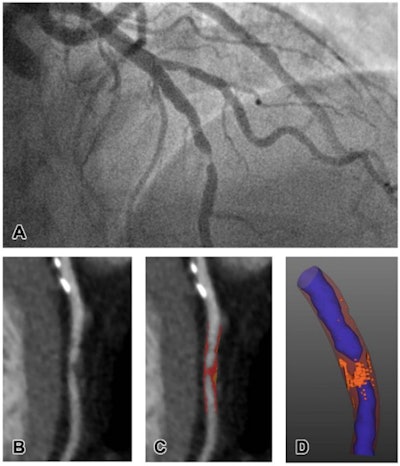

Representative images of CT plaque analysis demonstrate differences between type 1 and type 2 myocardial infarction. (Left panel) Images in a 42-year-old man diagnosed with type 1 myocardial infarction. (A) Image from invasive angiography demonstrates severe stenosis in the distal left anterior descending artery. (B) CT coronary angiogram, curved planar reformation, (C) quantitative plaque analysis, and (D) three-dimensional quantitative plaque analysis demonstrate a high burden of low-attenuation plaque. Right panel: Images in a 74-year-old man diagnosed with type 2 myocardial infarction. Images courtesy of the RSNA.Meah and colleagues sought to confirm whether particular kinds of heart plaque characterized on CTCA could help clinicians determine the type of heart attack a patient was suffering via a study that included 327 patients. Of the total cohort, 155 had type 1 infarction, 36 had type 2, and 136 had chest pain but no heart attack.

CTCA results showed that patients with type 1 heart attack had greater total, noncalcified, and low-attenuation plaque burdens compared with those patients with type 2. The presence of low-attenuation plaque was confirmed to be an independent predictor of type 1 attack, with an odds ratio of 3.44 (1 is reference standard).